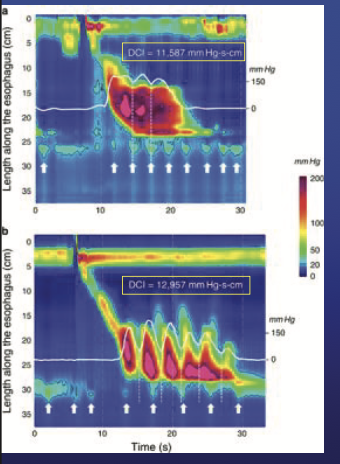

1. Distal contractile integral (DCI)

*normal 450<DCI <8000

Hypercontractile Esophagus

DCI >8,000

normal IRP